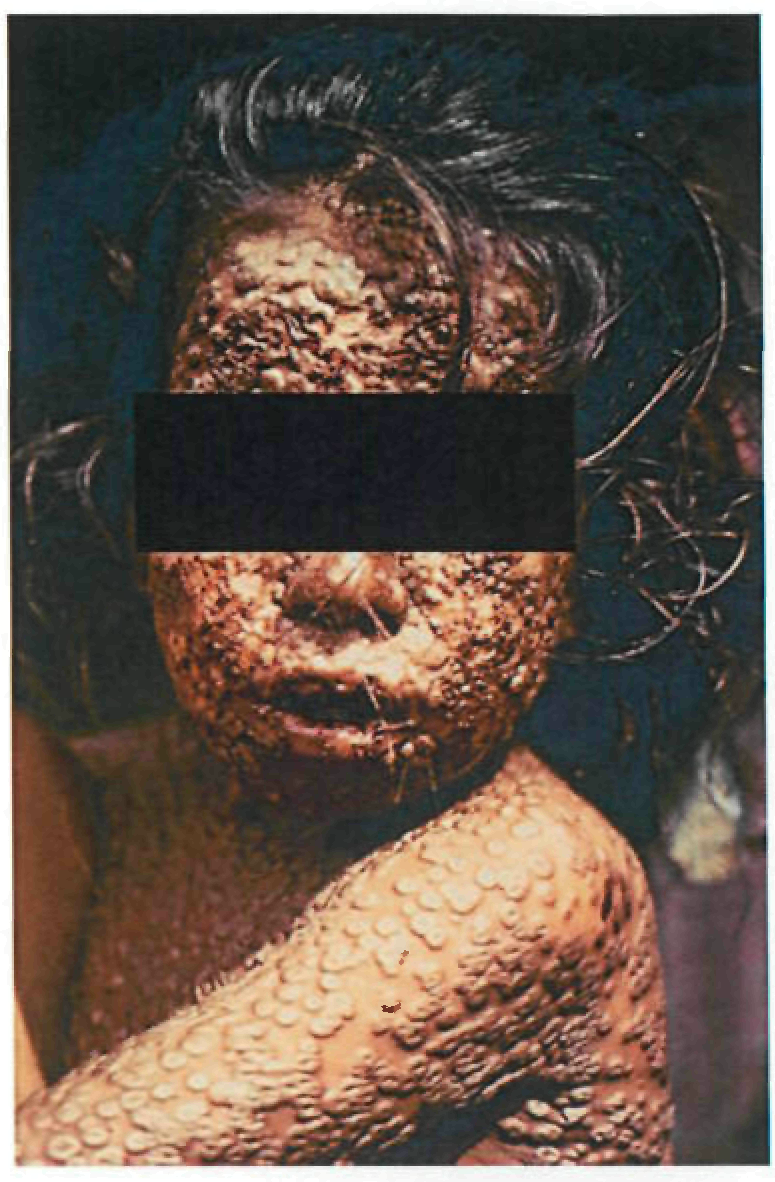

В 95% случаев сыпь поражает лицо, в 75% - ладони и подошвы, что является отличительным признаком заболевания. Также поражаются слизистые оболочки полости рта (в 70% случаев), половые органы (30%), конъюнктива и/или роговица (20%). У части пациентов имеет место проктит с поражениями перианальной области изолированно или в сочетании с высыпаниями в области гениталий [39]. Количество элементов сыпи варьирует от единичных до нескольких тысяч [13].

Степень тяжести заболевания зависит от числа элементов сыпи:

- Легкая (<25 элементов сыпи);

- Умеренная (25-99 элементов сыпи);

- Тяжелая (100-250 элементов сыпи);

- Крайне тяжелая (>250 элементов сыпи).

При формировании пустул вновь повышается температура тела, нередко до 39-40°С, состояние больных значительно ухудшается, развиваются тахикардия, артериальная гипотензия, одышка, сильный зуд кожи. Возможны диарея, лимфаденит (чаще шейный и паховый).

Оспа обезьян обычно разрешается самостоятельно, симптомы заболевания длятся от 2 до 4 недель [13]. Заболевание протекает легче у лиц, ранее вакцинированных против натуральной оспы. У вакцинированных пациентов сыпь менее интенсивно выражена и возникает в меньшем количестве по сравнению с невакцинированными [27]. При тяжелом течении риск летального исхода сохраняется в течение 2 недель после начала высыпаний. Показатель летальности при МРХ, вызванной штаммом западноафриканской клады, в среднем составляет 3% [13].

Осложнения оспы обезьян связаны преимущественно с присоединением вторичной бактериальной инфекции: абсцессы, флегмоны, бронхопневмония, кератит (с возможной потерей зрения), гастроэнтерит с диареей и рвотой, энцефалит, сепсис, септический шок. Развитие неблагоприятных исходов и осложнений МРХ наблюдается реже среди пациентов, вакцинированных против натуральной оспы [28].